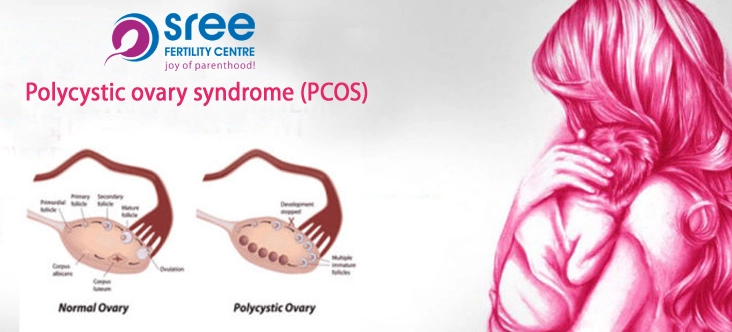

What Is Polycystic Ovary Syndrome(PCOS) ? Polycystic ovary syndrome (PCOS) is a complex condition that disturbs a woman’s hormone levels. It is a very common condition